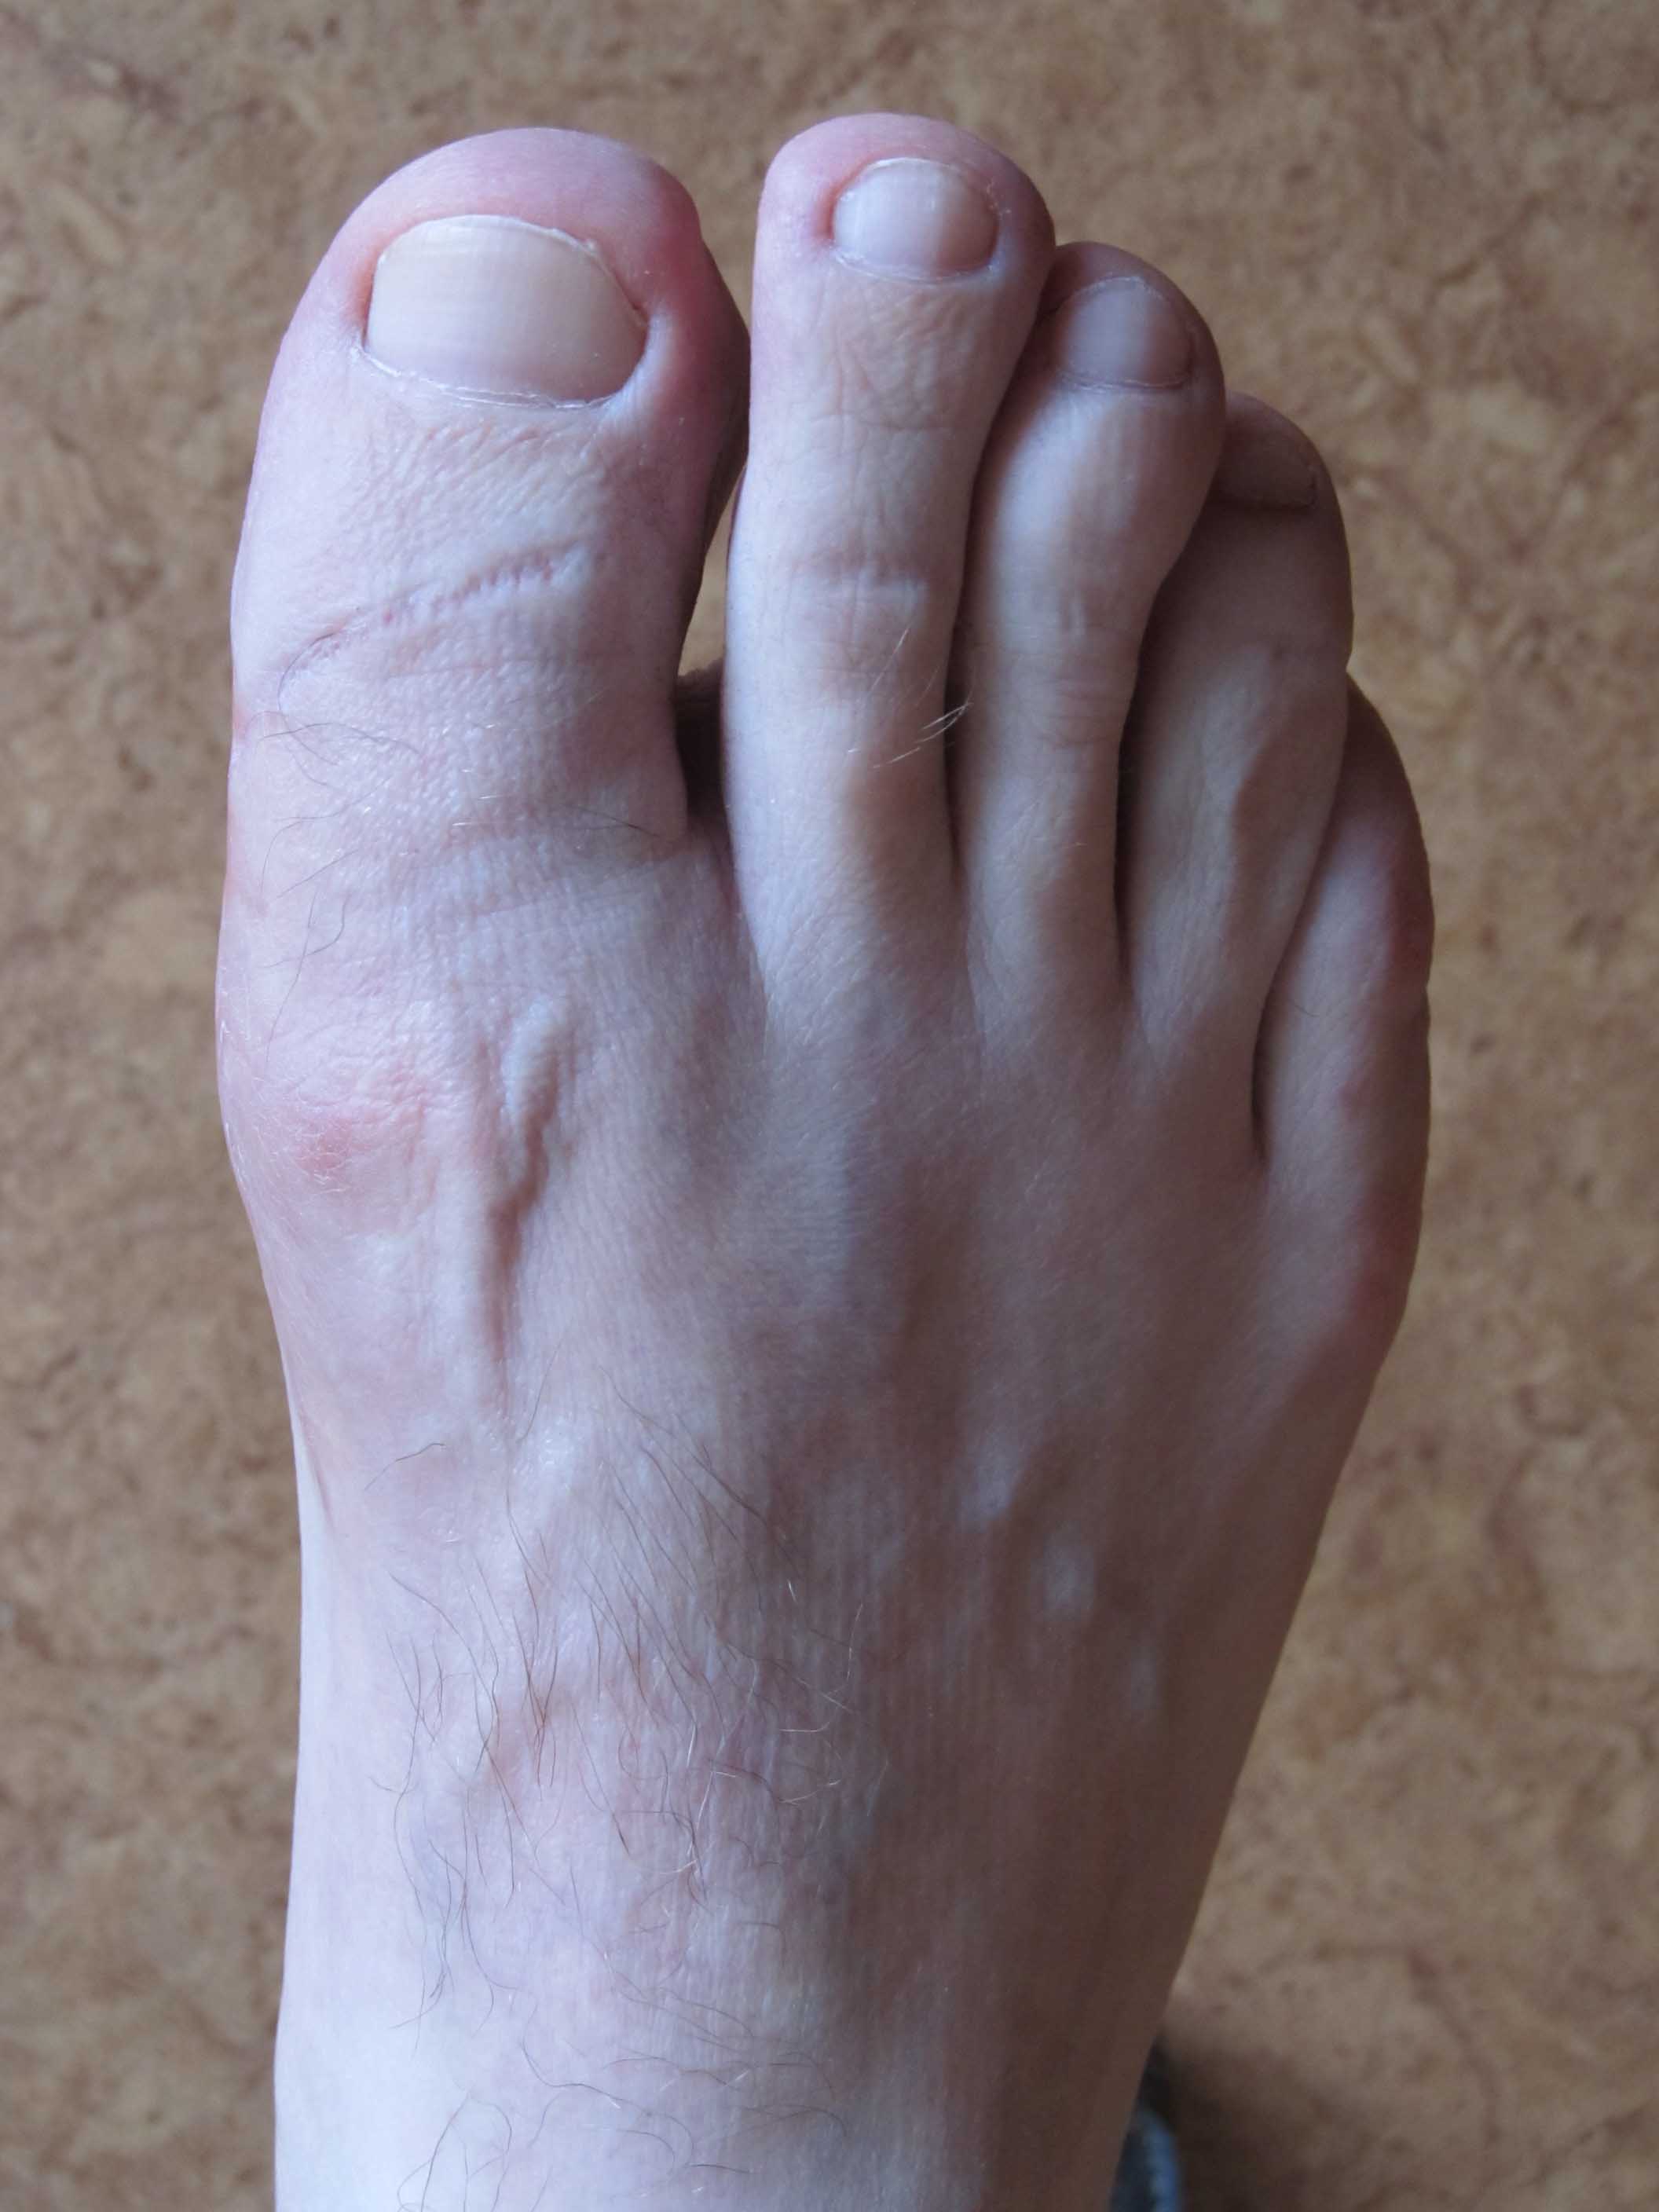

Здравствуйте, коллеги. Помогите с тактикой дальнейшего лечения.Мужчина 52 года, активный

физически. В марте 2012 оперирован по поводу ДОА плюсне-фалангового сустава 1 пальца,

сделана резекция основания основной фаланги и остеофитов головки плюсневой кости.

Послеоперационное лечение: массаж, физиотерапия. В настоящее время беспокоят сильные

боли в суставе, сохраняется ограничение движений. Дальнейшая тактика: артродез ПФС?,

Эндопротезирование ПФС?, повторная резекция основной фаланги? Мнения наших коллег

разделились. На фотографиях: вид стопы в настоящее время, рентгенограммы до операции,

после операции, в настоящее время. Прошу прощения за неважное качество снимков.